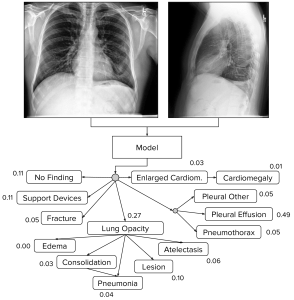

A great deal of thought has gone into this label structure. Instead of simply labelling a series of keywords, Stanford has designed a tree ontology, much like we saw in a famous Stanford (different team) dermatology paper by Esteva et al.

The labels have a hierarchical structure, based on visual appearances. For example, cardiomegaly (an enlarged heart) is a subset of “enlarged heart contours”, which also contains things like blood vessel enlargement (aortic aneurysm for example).

This structure will be very useful for training models. Lung opacities for example are made up of a common set of visual features, to the point that distinguishing between subclasses can be impossible in clinical practice. The superclass label provides a very useful additional signal to the model, which might help models focus on the important visual features that are common between the subclasses rather than learning to exploit non-pathological features (like what sort of scanner was used).

The labels make a good deal of sense as well. The team relied on the Fleischner society glossary (pdf link), a list of chest imaging descriptors produced by the experts in chest imaging interpretation. Notably, “infiltrate” has been excluded as a term (the Fleischner society does not recommend its use, because it is applied so inconsistently), and consolidation and pneumonia are considered equivalent (see the tree above, they have a link between them). It is impossible to differentiate these appearances on imaging alone, so this makes a lot of sense.

If you are wondering why these numbers don’t match the tree ontology from above, that figure is actually describing the model predictions. So the model predicts that 11% of cases have support devices, but the labels identify these devices in 56% of cases.